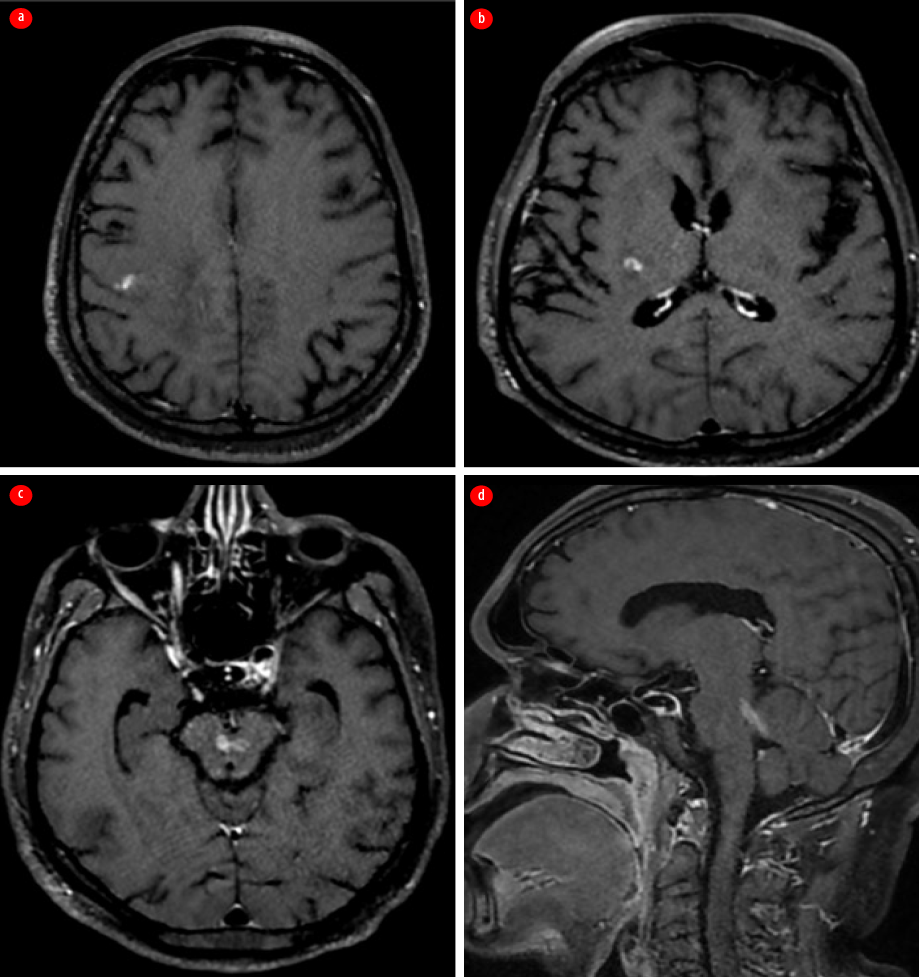

However, one month later, while still on oral co-trimoxazole, the patient presented with fever, headache, recurrent left focal motor seizures, and eventually fell into a coma, necessitating mechanical ventilation. Repeat contrast-enhanced MRI of the brain revealed irregular, streak-like enhancing areas with surrounding edema, originating in the precentral gyrus of the right frontal lobe and extending to the posterior limb of the internal capsule and the midbrain via the cerebral crus. It was noted to cross the midline at the level of the red nucleus. This irregular enhancement was also noted to involve the superior cerebellar peduncle [Figure 3].

Figure 3: Contrast-enhanced MRI of the brain taken following the first relapse. (a) Axial section shows irregular streak-like enhancing areas starting at the right prefrontal gyrus; (b) Axial section shows extension of enhancement along the right posterior limb of the internal capsule. (c) Axial section shows involvement of the midbrain with crossing of the midline. (d) Sagittal section indicates entry into the cerebellum via the left superior cerebellar peduncle.